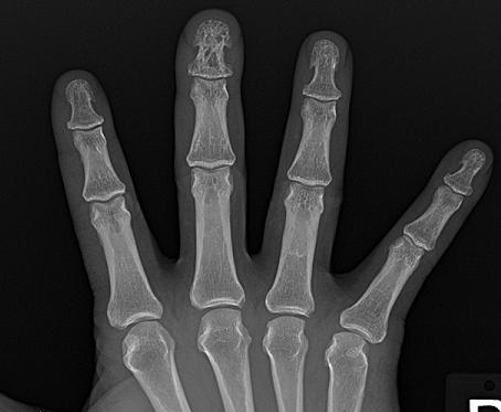

Lace-like cystic lesions in the phalanges of the hands

sarcoid